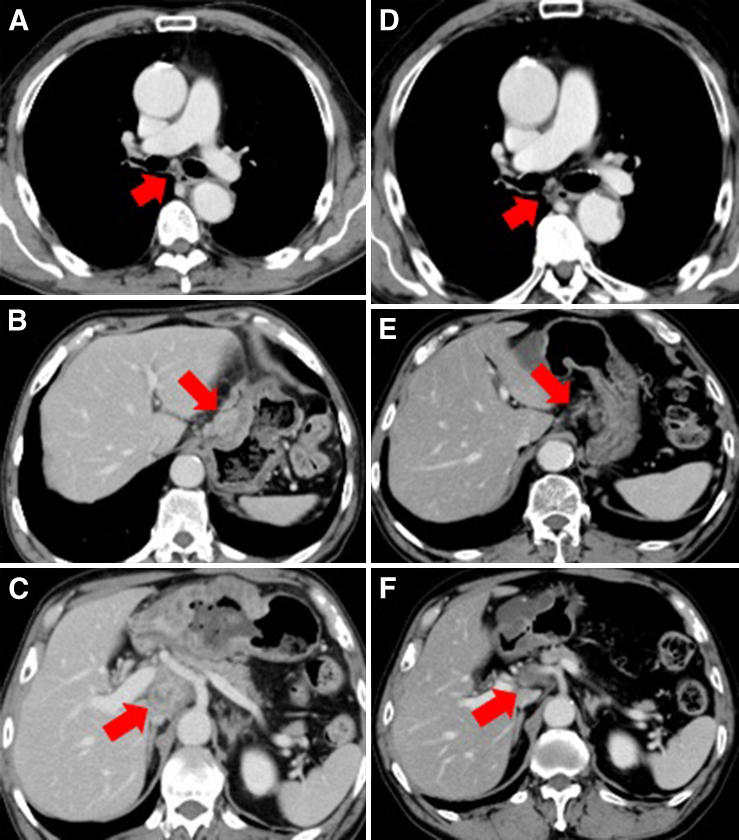

造影CT所見:胃前庭部前壁に不整な壁肥厚あり.胃大彎および小彎,右噴門部リンパ節腫大あり.肝門部・気管分岐直下にも腫大したリンパ節を認めた(Fig. 3A~C).

Chest-abdominal CT scan findings before chemotherapy showed lymph node metastases in #107 (A), #1 (B), #13a-12p (C). After chemotherapy, #107 and #13a-12p lymph node disappeared (D, F), and #1 lymph node had reduced in size (E).

治療経過:遠隔リンパ節転移を伴う進行胃癌と診断し,paclitaxel(50 mg/m3)+S-1(80 mg/day)療法を開始した.1コース施行後にHER2免疫染色検査の結果が判明した.噴門直下の病変は強陽性であり,胃角部の病変はHER陰性部が混在するものの,同様の性質であった(Fig. 2B).採血でも腎機能は改善傾向であったため,次コースからはtrastuzumab(初回8 mg/kg,2回目以降6 mg/kg)+cisplatin(60 mg/day)+capecitabine(3,000 mg/day)療法を開始した.2コース施行後のCTでは,気管分岐直下のリンパ節は縮小したが,肝門部から膵頭部背側にかけてのリンパ節腫大は大きさに変化が見られなかった.7コース施行後に手足症候群にてcapecitabineを20%減量(2,400 mg/day),8コース終了後に食思不振のためさらに減量(1,800 mg/day)とした.10コース施行後のCTでは胃壁の濃染部がわずかに縮小を来し,17コース施行後のCTでは,肝門部から膵後面にかけてのリンパ節は縮小し,気管分岐直下のリンパ節も縮小を維持した(Fig. 3D~F).根治切除の可能性を考慮し,上部消化管内視鏡検査を行うと,胃角部前壁の3型腫瘍は瘢痕化し,噴門直下の病変は消失した(Fig. 1C, D).PET-CTでもリンパ節を含めて集積はなく,治癒切除が可能であると判断した.化学療法開始から1年5か月後に幽門側胃切除術,D2+#8p・#13リンパ節郭清,胆囊摘出術,Roux-en-Y再建を施行した.術前検査で噴門部病変は消失しており,術後の食欲低下を懸念したため噴門病変は切除しない方針とした.